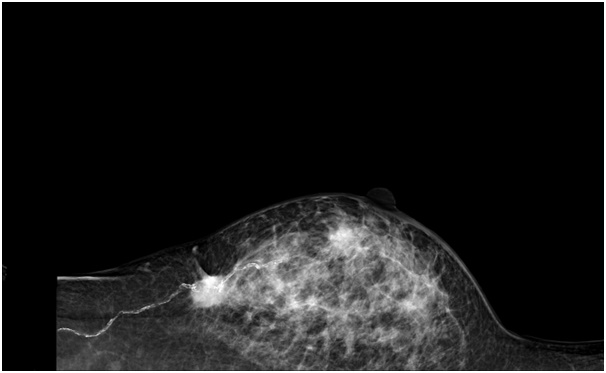

유방에 어떤 증상이 있게 되면 검사는 3가지로 진행되게 됩니다. 첫 번째로 신체검사입니다. 유방을 직접 보고, 손으로 촉진하여 이상의 유무를 확인하게 됩니다. 그 다음으로는 유방 촬영과 유방 초음파가 있습니다. 유방 촬영은 유방 촬영기를 이용하여 유방을 넓게 편 뒤에 방사선을 발생시켜서 촬영하게 됩니다. 유방의 비대칭적인 부분이나 석회화 등을 주로 찾아 보게 됩니다. 유방 초음파는 방사선을 발생시키지 않고 말 그대로 초음파를 발생시켜서 검사를 하게 됩니다. 초음파는 주로 결절, 즉 혹을 잘 찾는 검사입니다. 기본적으로는 이렇게 3가지 검사를 함께 진행하게 되지만 상황에 따라서 어떤 검사를 할 것인가는 차이가 있습니다.

그렇다면 40세 이상의 여성분들은 어떨까요? 위에 말씀드린 ACR(American College of Radiology) 권고안에 따르면, 40세 이상인 분들은 유방 촬영을 먼저 권고하고 있습니다. 유방 촬영을 하고 그 결과가 이상이 없는 경우라면 검사를 종료하고 이상이 생기게 되면 유방 초음파와 조직 검사를 진행하라고 되어 있습니다. 우리 나라에서도 그렇게 진행하면 될 것 같습니다. 그런데 한 가지 말씀드리고 싶은 부분이 있는데, 우리나라 여성분들의 유방은 치밀 유방이 많아서 유방 촬영 만으로는 잘 보이지 않는 경우가 많습니다. 그래서 유방 초음파를 병행하는 환자들이 대부분일 것으로 생각됩니다.

정리하면, 40세 미만의 여성에는 멍울이 만져진다면 신체검사 후, 유방 초음파 검사를 하고, 검사상 특별한 문제가 없으면 경과 관찰을 하게 되고, 검사상 암이 의심된다면 유방 촬영과 조직 검사를 하게 된다고 알고 계시면 될 것 같습니다. 그리고 40세 이상이시라면 유방 촬영을 먼저 하고 그 결과에 이상이 있거나 검사가 부족하면 유방 초음파 및 조직 검사를 하게 된다고 알고 계시면 될 것 같습니다.